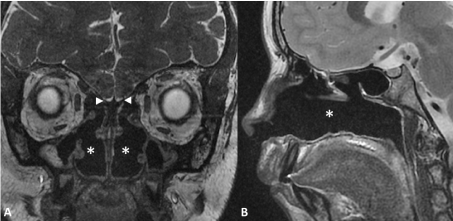

In the syndromic association of CA, atrophic rhinitis, bronchiectasis and CVID (Figure 3) and in the CHARGE syndrome MRI showed complete aplasia of the OB. These two patients had complete anosmia.

Figure 3: Congenital anosmia and atrophic rhinitis in a 12-years-old child.

MRI of aplastic olfactory bulbs associated with severe atrophic rhinitis on coronal Fast Imaging Employing Steady-state Acquisition, FIESTA (A) and sagittal T2-weighted imaging (B). The olfactory fossae (arrowheads) does not contain any olfactory bulb. The other major finding is empty nasal cavities (star) with atrophic turbinates and hypoplasic paranasal sinuses. View Figure 3